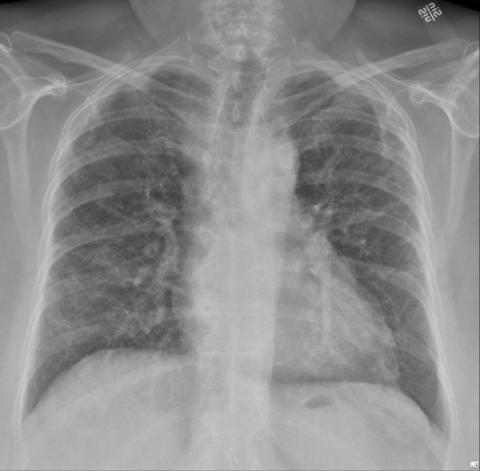

På billedet ses spredte lungeforandringer hos en patient med COVID-19. Billedet er taget 6 uger efter udskrivelsen. Kilde: Infektionsmedicinsk afdeling, OUH.